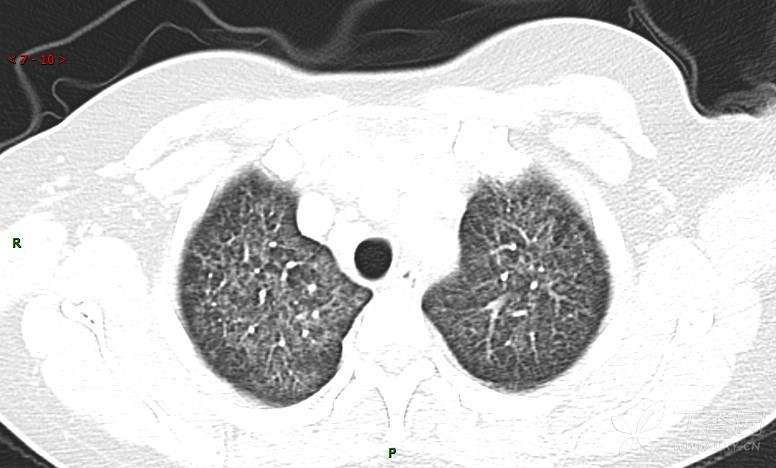

肺内弥漫性网状结节影,PET-CT却无阳性病灶,这是?(附其他2例链接)

女性,58岁,阵发性咳嗽2月,加重1月。

糖类抗原15-3 70.7 U/ml ↑ 0--31.3

癌胚抗原 57.12 ng/mL ↑ 0--5

糖抗原125 166.8 U/ml ↑ 0--35

细胞角蛋白19片段测定 8.32 ng/ml ↑ ≤3.3

糖抗原199 901.79 U/ml ↑ 0--37

患者活检肺组织后行PET/CT检查